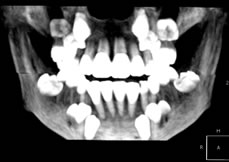

VR(ボリュームレタリング)

VR(ボリュームレタリング)では表面から内部のデータもあらわした三次元構成です。 ![]() ![]() |